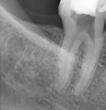

In the past years the heat-treated Ni-Ti rotary files have become a gold standard in endodontics. However, heat-treated nickel-titanium endodontic instruments produced with the electro discharged machining are on a completely another level offering some unparalleled properties. Scientific studies show surprisingly high values of cyclic fatigue resistance, increased cutting efficiency and increased wear resistance with low degradation. The HyFlex EDM files systems offer the user a simple, predictable, safe, and cost-effective instrumentation in all clinical types of root canals, form straight to severely curved. The new OGSF sequence makes it possible to enlarge the root canal in a minimally invasive way to 30/0.04, making the EDM system even more versatile. If needed the root canals can be enlarged with EDM Hyflex 40/0.04, and further with the reducing taper from 50/0.03 to the file size up to 60/0.02 without loosing on the flexibility of the files to best preserve the original shape of the root canal all the way to the apex. Pre-bending the controlled memory EDM files also offers a simple management for by-passing ledges previously formed in the root canal. The HyFlex EDM system is the system of choice for beginners and advanced users.